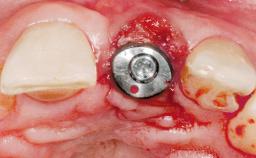

Immediate Placement of an Implant in a Maxillary Right Central Incisor Site

A 30-year-old female patient was referred to the office for the treatment of tooth 11. Her chief concern at the initial visit was to inquire, “Why is my tooth pink?” Upon clinical examination, it was determined that tooth 11 had a previous history of trauma and that the clinical crown had become noticeably pink in color as a result of internal resorption. This diagnosis was confirmed radiographically, indicating a large radiolucency involving the central and distal portions of the clinical crown. It was determined that restoration of this tooth was not possible, and that extraction was indicated. The presence of a mid-line diastema, which the patient wanted to reproduce, directed the treatment plan for tooth replacement utilizing a dental implant.

| Bone Augmentation | Horizontal|Simultaneous |

| Augmentation Materials | Autogenous chips|Membrane |

| Socket Integrity | Sufficient, with intact bone walls |

| Bone Volume | Sufficient, with intact walls |